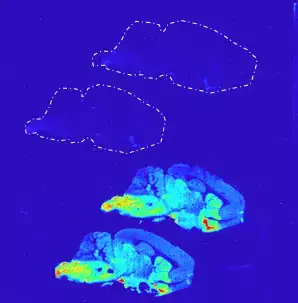

The Autoradiography Core facility is included in the Division of Imaging Core Facilities (Department of Clinical Neuroscience) and is part of the Centre for Imaging Research (CIR). We’ll help you with autoradiography (in vitro & ex vivo) and radioligand binding assays (cultured cells or tissue homogenates), using short- or long-lived radiotracers, for different types of projects, e.g. target-specificity, binding affinity, drug screening.

A highly accurate, quantitative, and high-throughput method used to study a range of pharmacological properties (binding kinetics and pharmacodynamics) of a radioligand or tracer to a specific target protein.